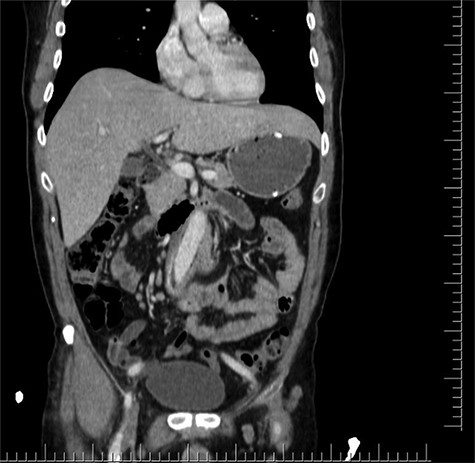

Axial section shows the two limbs of the EVAR, at the bottom. And on top of it, the Dacron straight graft part in the middle of the jejenum.

Distal CT axial section shows the two limbs of the EVAR, at the bottom. And on top of it, the Dacron straight graft part in the middle of the jejenum.